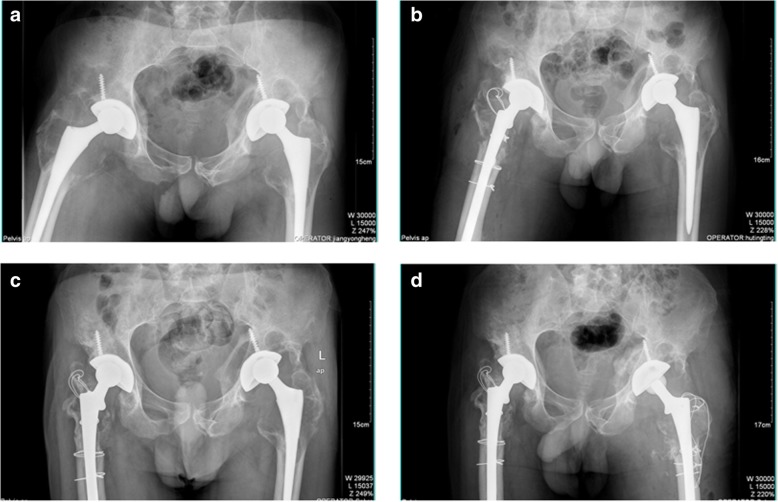

A 51-year-old male visited us complaining of right hip pain in June 2011. He had undergone bilateral THA more than 10 years prior. X-rays revealed wear of the acetabular linings of both hips, and severe osteolysis of the proximal femora and acetabula (Fig. 1a). Preoperative laboratory data revealed no sign of infection; we thus revised the right hip on June 24, 2011. During operation, we found that the acetabular cup was firmly fixed; we thus replaced the acetabular polyethylene lining and the alumina ceramic head. The femoral stem was loose so a DePuy Solution stem (diameter 12 mm) was placed after removing the old stem. The DePuy stem is a distally fixed, extensively porous-coated cylindrical revision femoral stem (Fig. 1b). We grafted alloallergic cancellated bone onto the acetabular side; we did not graft the proximal femoral bone defect. On April 11, 2013, we revised the left hip. Again, we found that the acetabular cup was firmly fixed and the femoral stem loose. We grafted alloallergic cancellated bone onto the acetabular side, replaced the acetabular polyethylene lining and the alumina ceramic head, and again used a DePuy Solution stem (diameter 12 mm) for femoral revision (Fig. 1c and d). However, on June 122,014, the patient returned to hospital complaining of left hip pain and an inability to move after changing his sitting posture. Blood tests revealed a normal erythrocyte sedimentation rate and a C-reactive protein level of 56.8 mg/L. A stem fracture was evident on X-rays (Fig. 2a and b). We revised the left hip 11 days later; the cup and acetabular polyethylene lining were satisfactory. We replaced the femoral head and used a 14-mm-diameter DePuy Solution stem to revise the femoral side. Allograft bone augmentation of the proximal femur followed by cerclage wiring was performed (Fig. 2c and d). However, the patient returned again in September 2017 with a right femoral prosthetic fracture (Fig. 3a and b). We replaced the femoral head and the acetabular polyethylene lining, and used a 14-mm-diameter Wagner SL stem (Zimmer, Warsaw, IN, USA) to revise the right hip. We performed allograft bone augmentation of the proximal femur followed by cerclage wiring (Fig. 3c and d).

Fig. 1.

a: Pre-operative anteroposterior (AP) radiographs taken in June 2011. The patient had undergone bilateral total hip arthroplasty more than 10 years prior. The X-rays revealed wear of the acetabular linings of both hips, and severe osteolysis of both proximal femora and acetabula. b: Radiograph taken after revision of the right hip in 2011. c: Pre-operative AP radiograph taken in 2013. d: Radiograph taken after revision of the left hip in 2013